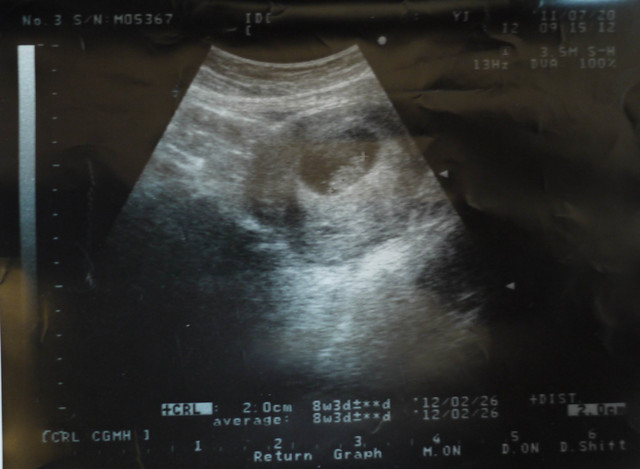

7/20我跟爸爸去做了第二次產檢

這次寶寶長到了2cm

比較同期張蓓蓓還要小隻一點

孕期才到8w3d